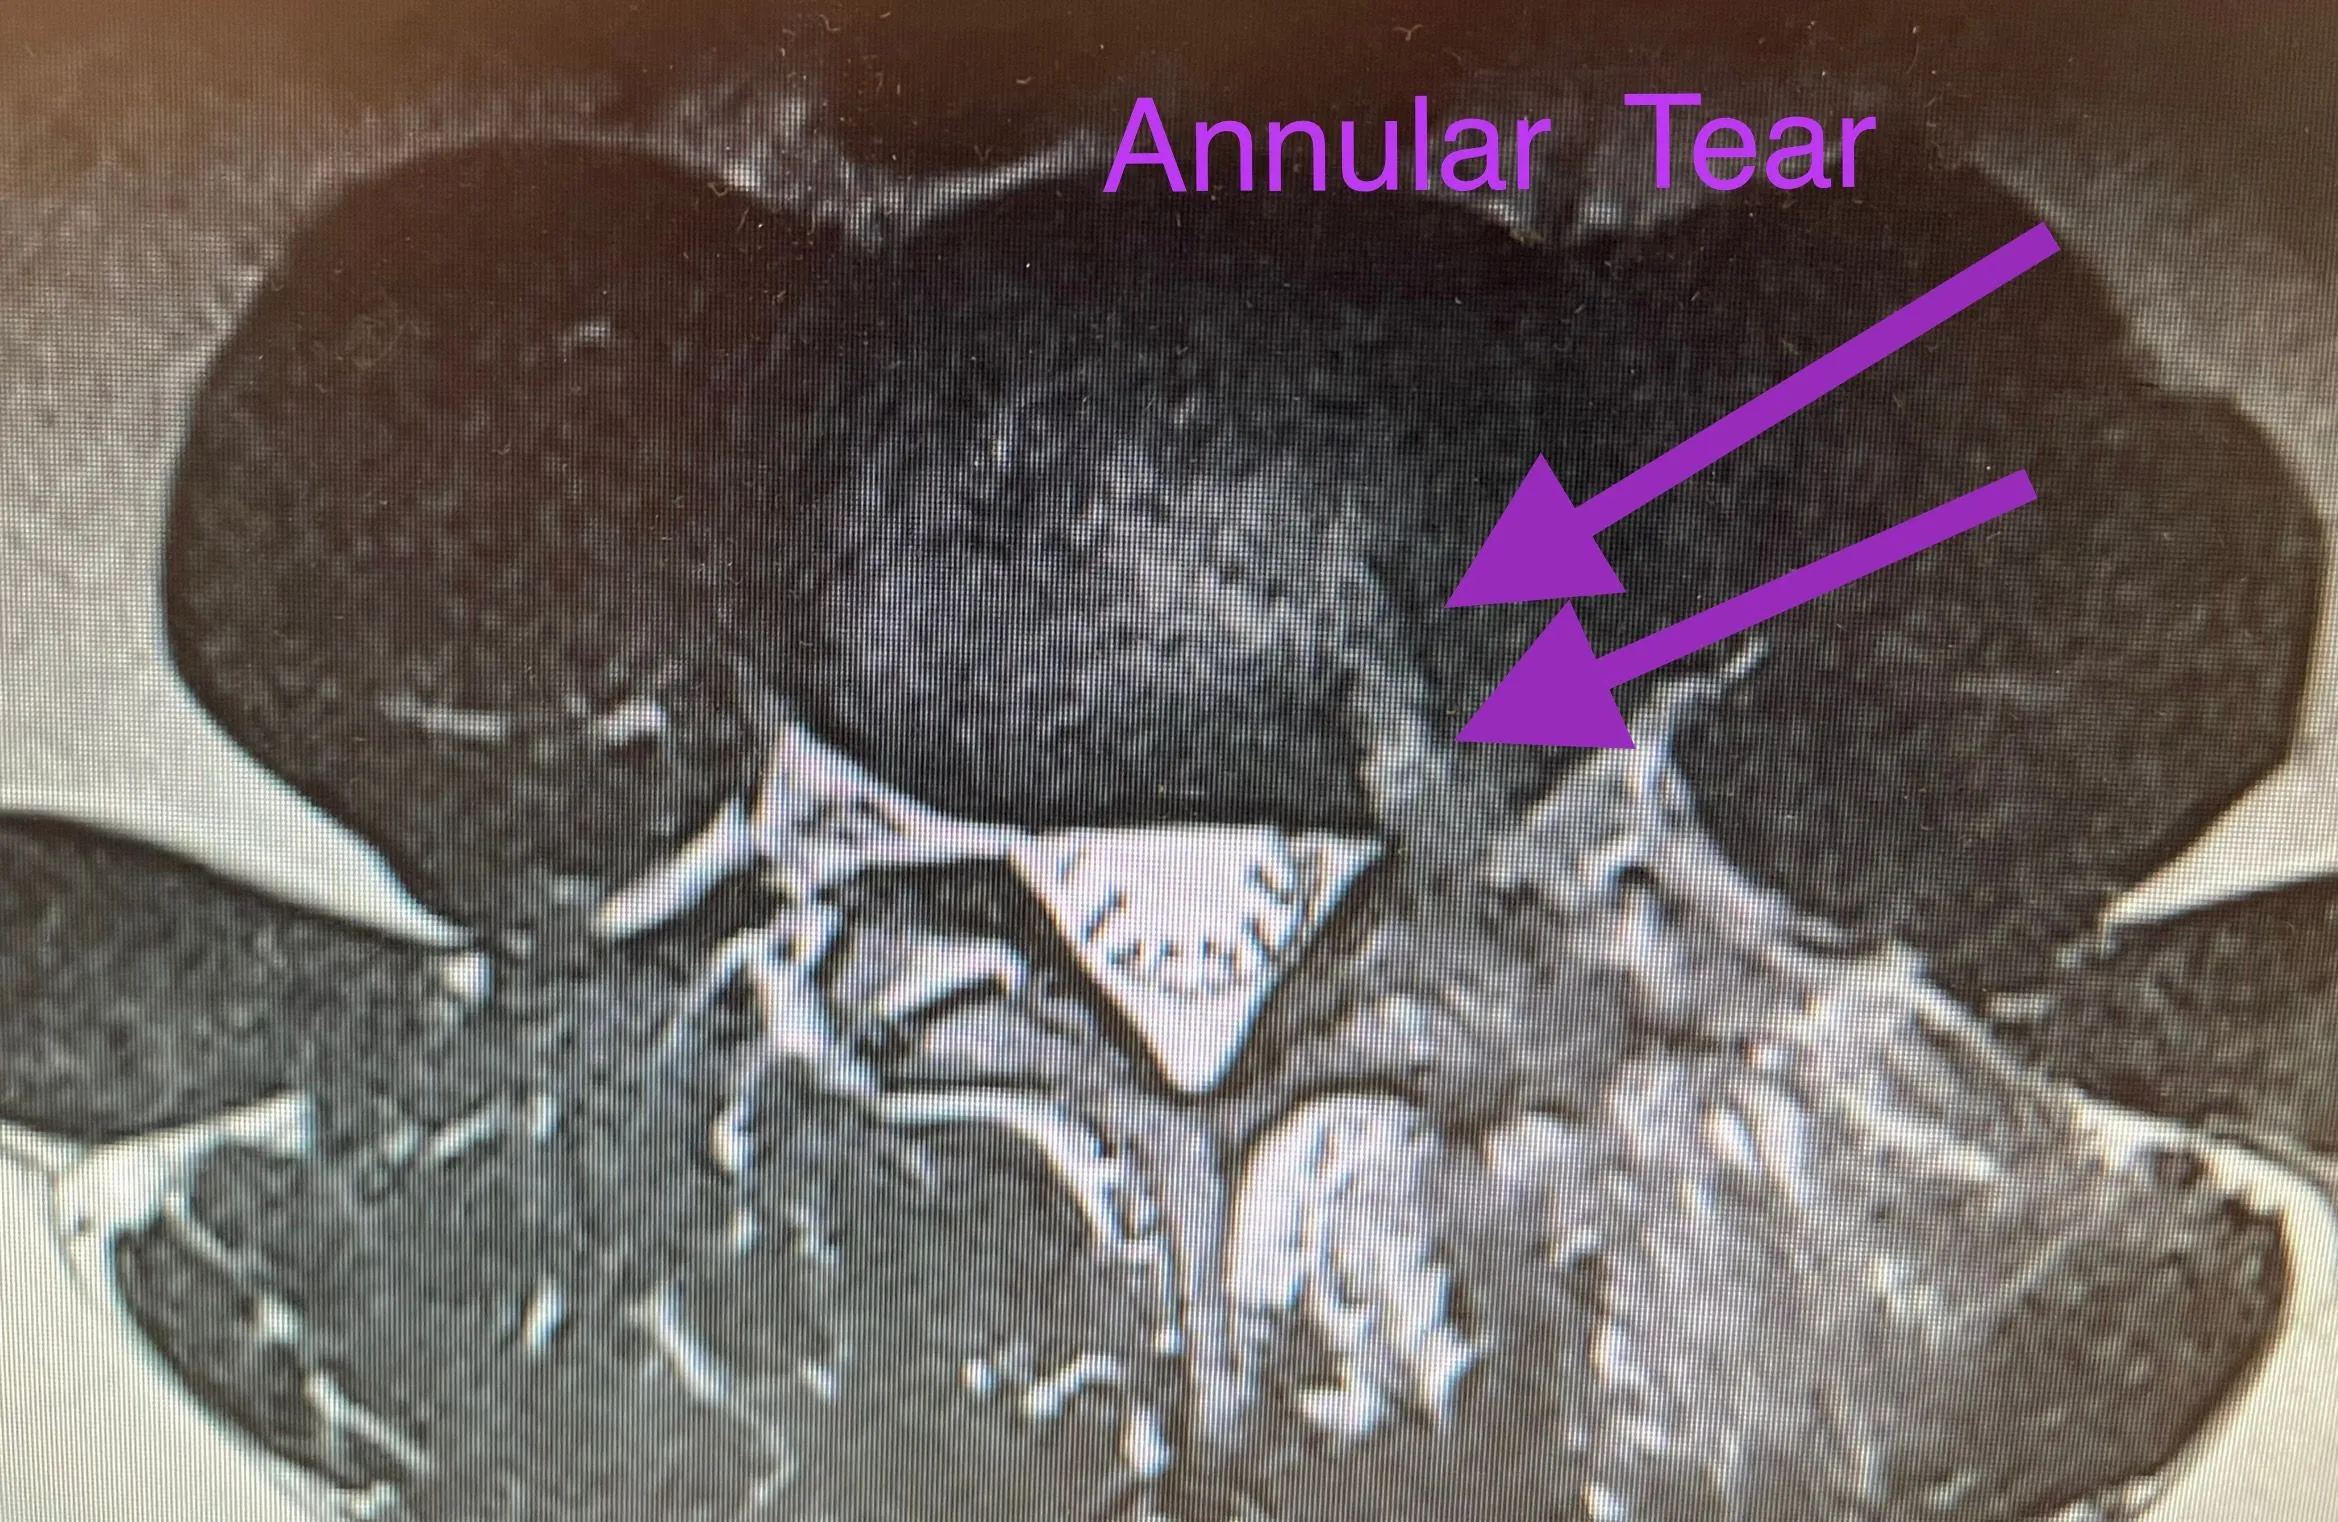

Deuk Laser Disc Repair is a laser spine surgery performed to cure back pain or neck pain associated with herniated discs, bulging discs, annular tears, sciatica, spinal stenosis, pinched nerves, and other conditions that cause chronic spine pain. Traumatic injuries to the disc can cause annular tears to form. The inflamed annular tear causes back pain or neck pain. Inflammation of the surrounding nerve roots can cause leg or arm pain.

Unfortunately, the disc’s outer wall, the annulus fibrosus, can develop traumatic tears (annular tear), allowing the jelly-like nucleus pulposus to push backward out of the tear into the spinal canal or neural foramen.

Untreated disc inflammation can lead to degenerative disc disease. The pain in your back from degenerative disc disease comes from irritated (inflamed) nerve fibers within the nearby annular tear.